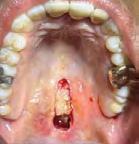

Figura 1. Fotografía inicial.

Paciente masculino de 29 años de edad, sin antecedentes médicos de interés acude al servicio de Cirugía Maxilofacial, el cual acude a la con sulta por odontalgía asociado al pri mer molar inferior izquierdo (Figura 1). Realizamos estudios radiográficos de dicho órgano (Figura 2), siendo valorado por especialista en prótesis y endodoncia quienes refieren no ser candidato para rehabilitación y tra tamiento de conductos con un pro nóstico poco favorable. Motivo por el cual se ofrece la opción de realizar TD del tercer molar inferior izquierdo al lecho quirúrgico del primer molar

Figura 3. Alveolos dental postextracción de primero y tercer molar inferior izquierdo. Figura 4. Punto de sutura en cruz para estabilidad de tercer molar inferior izquierdo y cierre del resto de las heridas. Figura 5. Radiografía dentoalveolar postoperatoria.